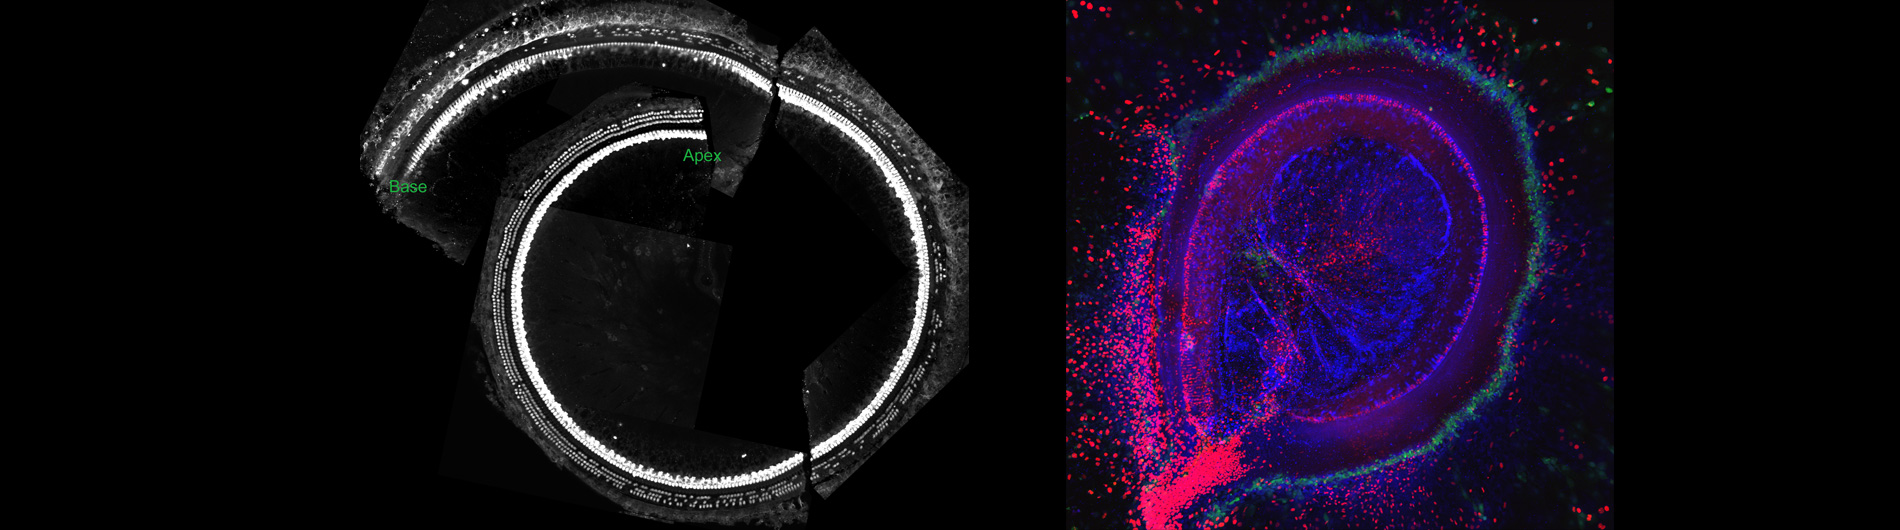

Dissected mouse cochlea with hair cells in red and supporting cells in green. Featured on the cover of Nature.

Hearing loss results from prolonged noise exposure. Individual genetics determines each person’s threshold for damage, and by the age of 65 around one third of adults complain of hearing loss. Age-related and noise induced hearing loss are both incurable and progressive, and in many cases are due to the accumulated loss of cochlear mechanosensory hair cells. Sensory hair cells are arrayed in a highly structured epithelial sheet, surrounded by supporting cells with differing shapes and functions. Mammals only generate these specialized cells during fetal development. Once sensory hair cells are lost through over-stimulation, they are never replaced. The adjacent supporting cells expand without cell division to fill the space and create a scar that is insensitive to sound vibrations.

During my post-doctoral collaborations, we found that purified immature mammalian supporting cells can also divide and differentiate into new sensory hair cells under certain conditions in culture. Moreover, mature mammalian supporting cells can differentiate into sensory hair cells, either in vitro or in response to induction with certain genes. Our findings suggest that sensory hair cell regeneration in mammals may be feasible. Understanding the molecular controls that regulate the processes of regeneration, however, will be key to designing therapies for regenerating sensory hair cells.